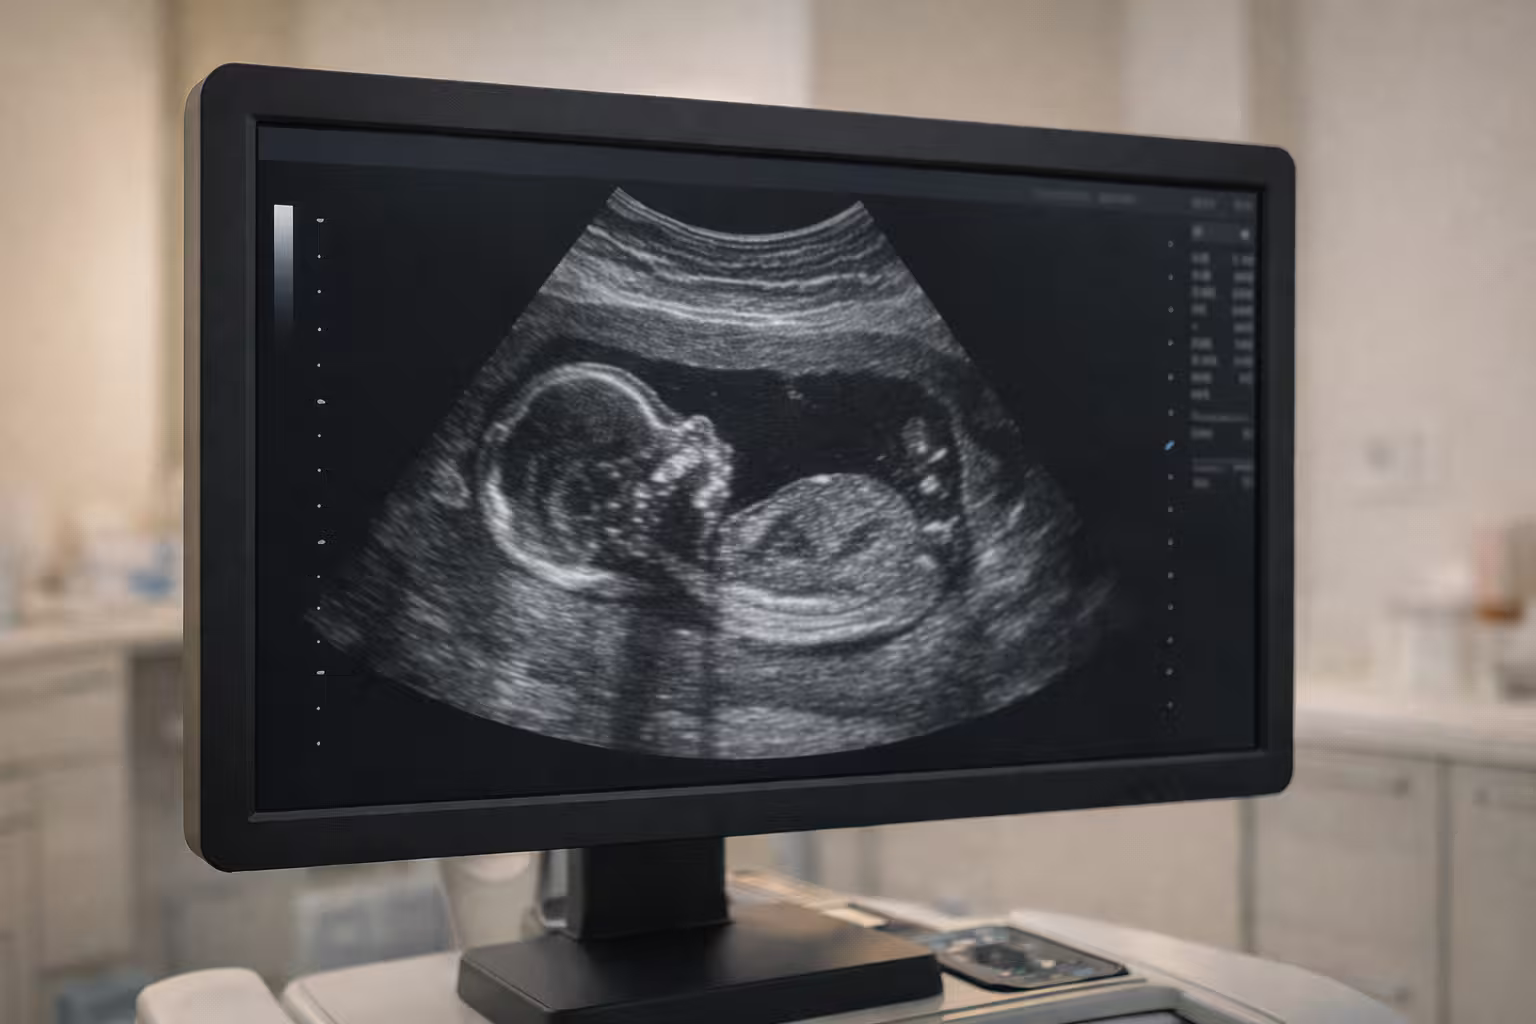

Ultrasonido estructural desde $2,500.00 en Polanco. El ultrasonido estructural del segundo trimestre, también llamado ultrasonido morfológico, es un estudio que se realiza entre las 18 y 22 semanas de embarazo para evaluar de forma detallada la anatomía del bebé.